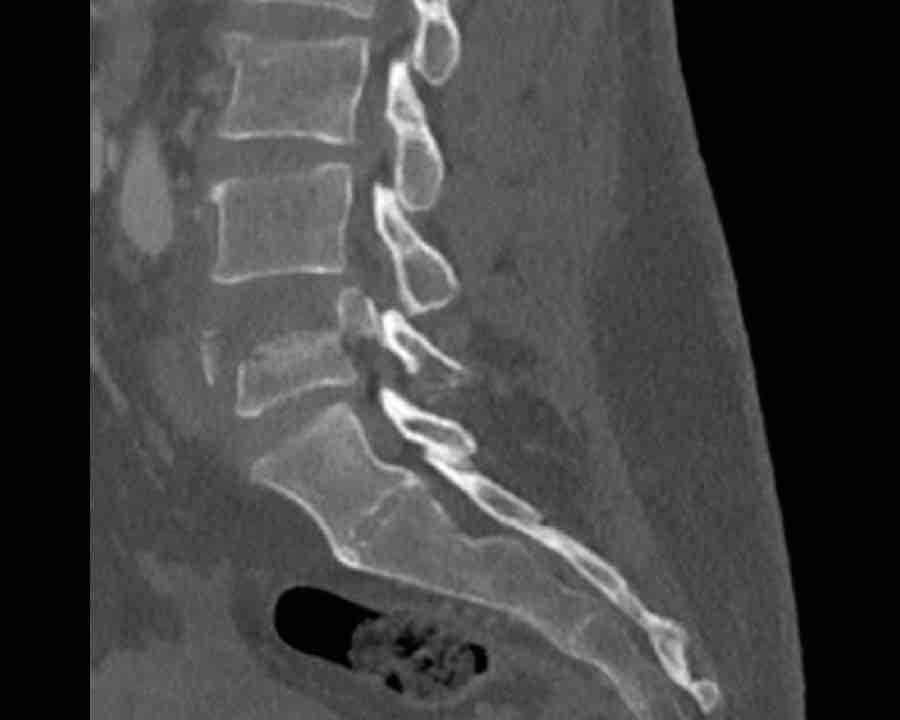

B3 Extension distraction injury

Hyperextension can result in distraction of the anterior tension band, which is formed by the vertebral bodies, the anterior and posterior longitudinal ligaments and the intervertebral disc.

These injuries can be difficult to detect since patients are scanned in the supine position laying on their back, which may obscure the anterior distraction.

However, these injuries mainly occur in patients with a rigid spine as a result of osteoarthritis, DISH or Ankylosing Spondylitis (SpA).

Stay persistent when examining a patient with a rigid spine until you have found the B3 injury.

Extension distraction is characterized by:

- Distraction of the tension band on the anterior side.

- Any horizontal or oblique fracture line through vertebral bodies anteriorly with separation on both sides.

- Widening of intervertebral disc space.